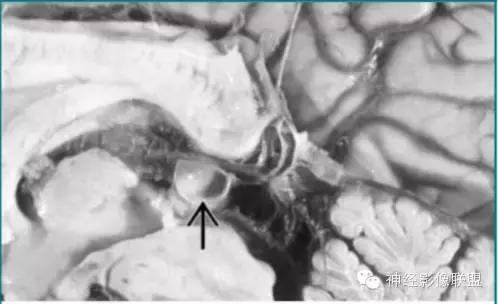

神经脑囊虫病